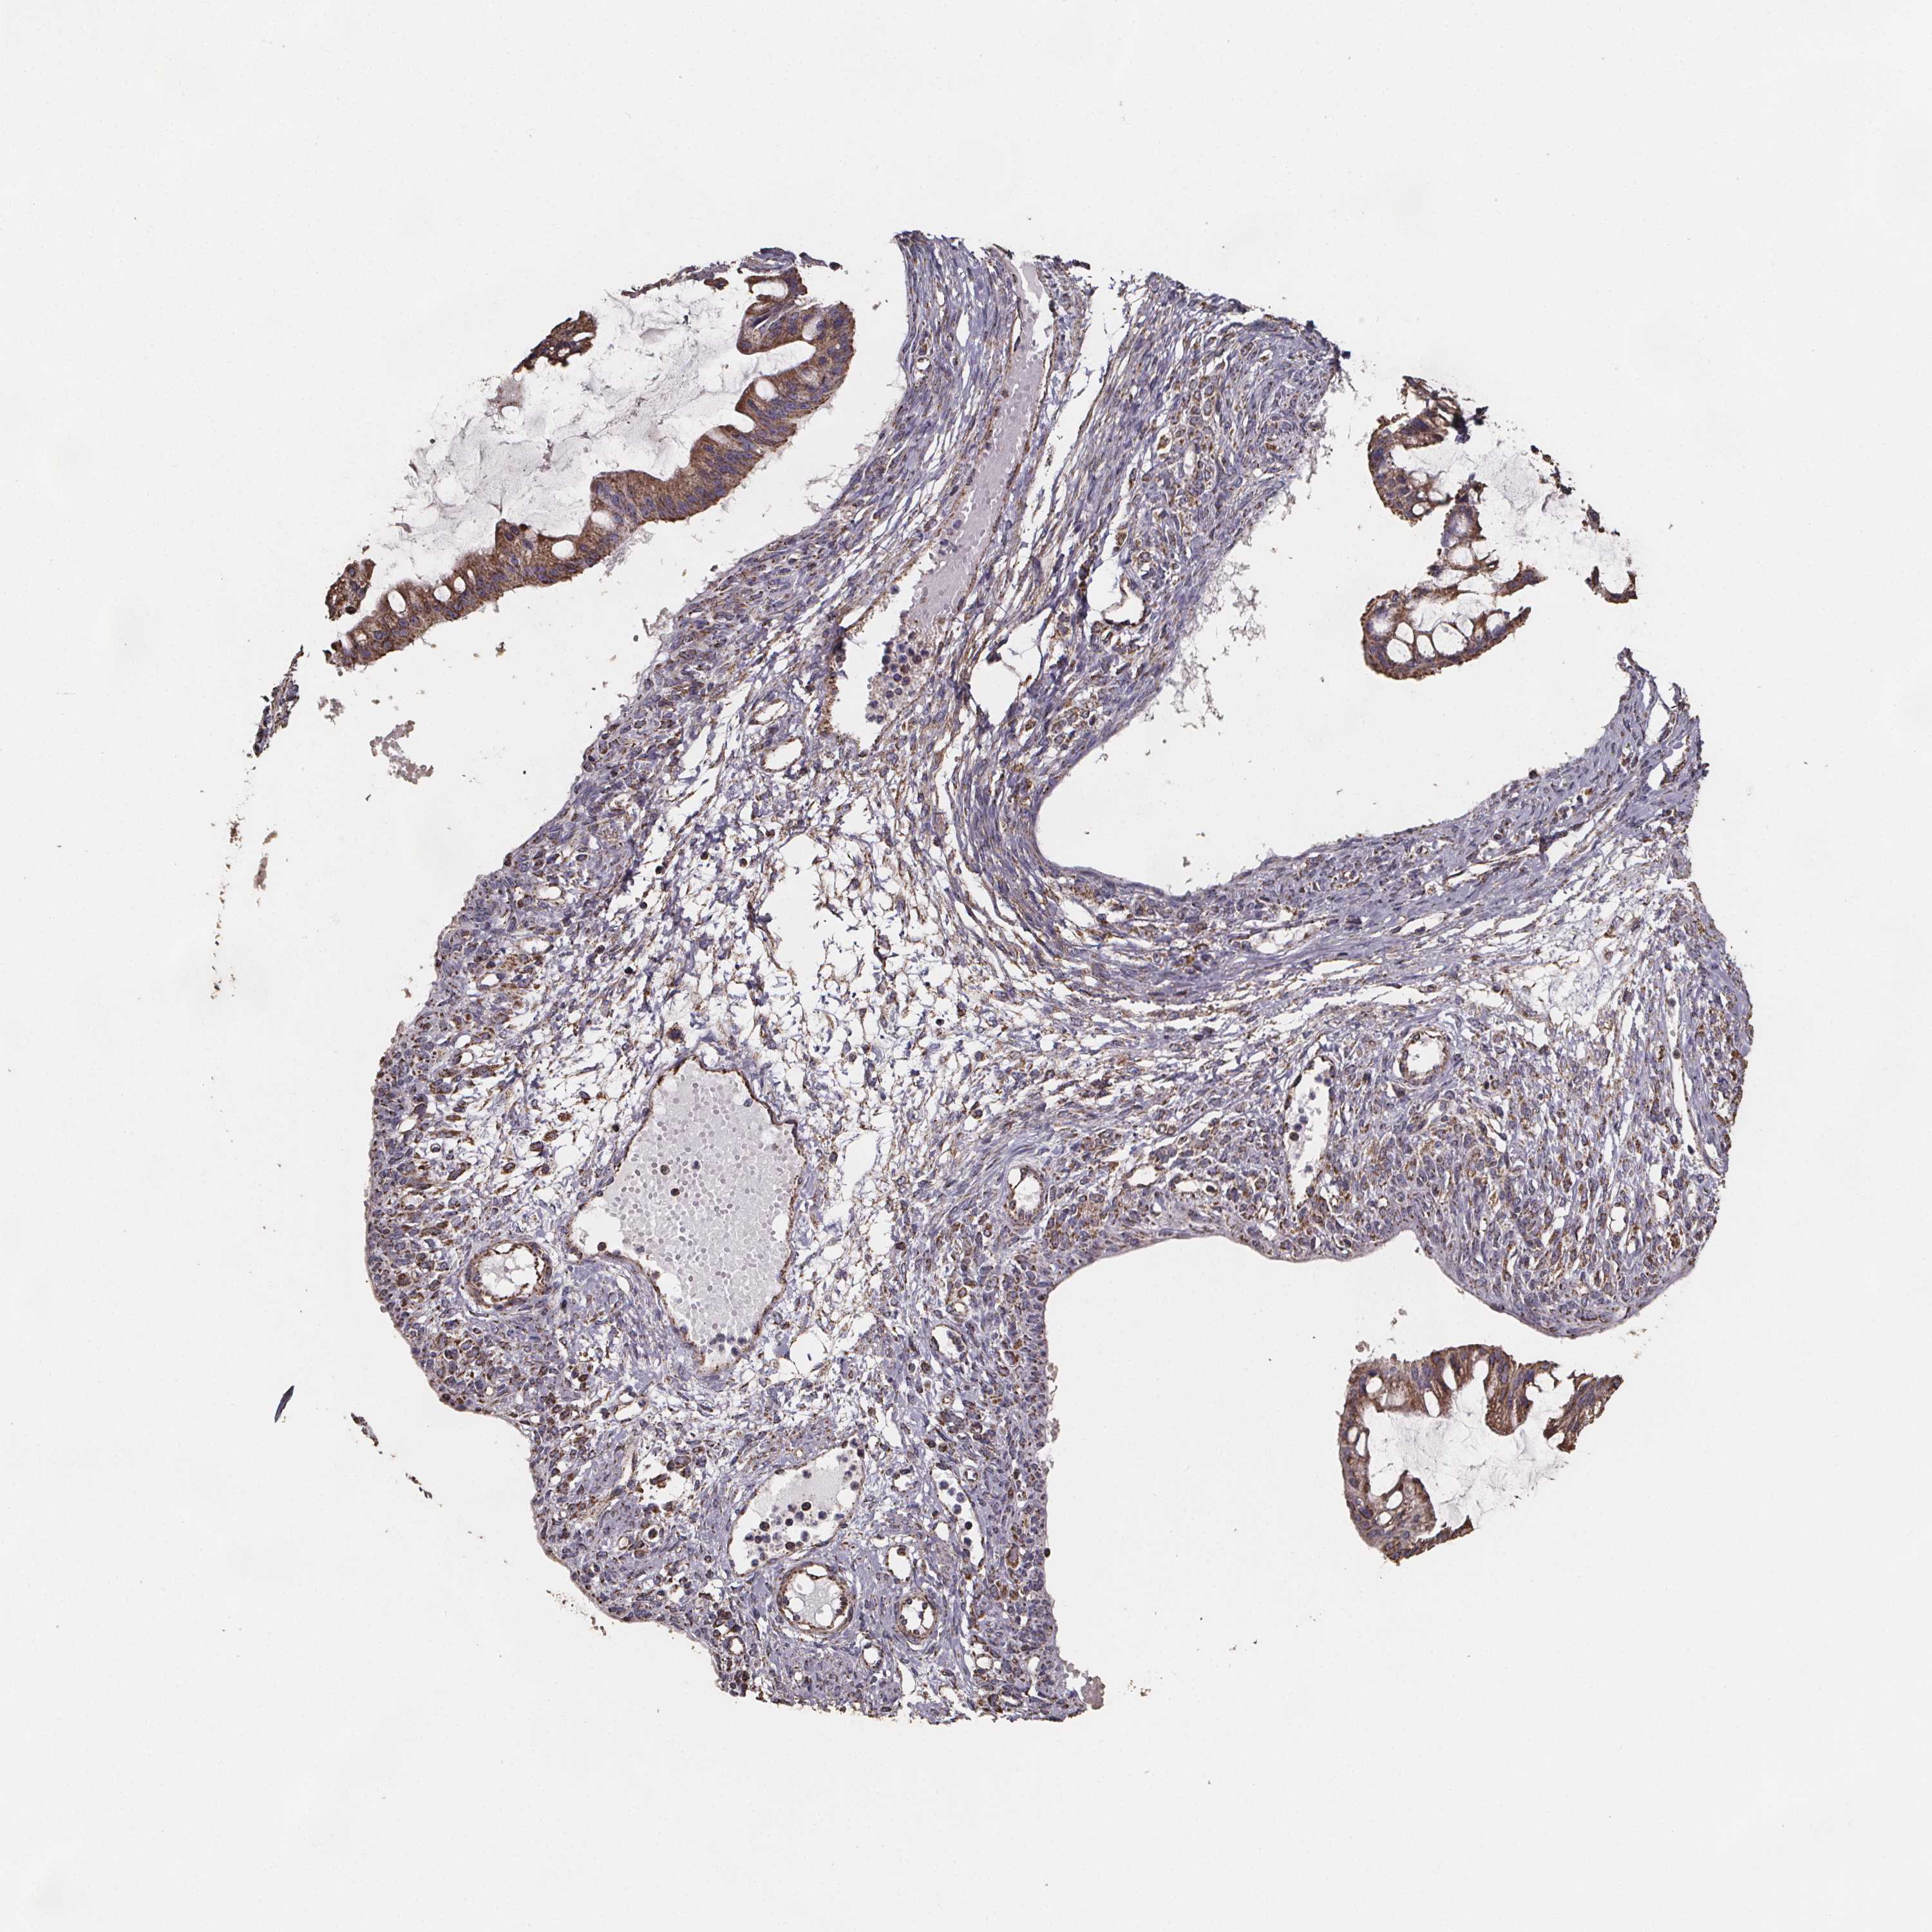

OVARIAN CANCER - Protein expressioni

A mouse-over function shows sample information and annotation data. Click on an image to view it in a full screen mode. Samples can be filtered based on level of antibody staining by selecting one or several of the following categories: high, medium, low and not detected. The assay and annotation is described here.

Note that samples used for immunohistochemistry by the Human Protein Atlas do not correspond to samples in the TCGA dataset.

Antibody stainingi

Antibody staining in the annotated cell types in the current human tissue is reported as not detected, low, medium, or high, based on conventional immunohistochemistry profiling in selected tissues. This score is based on the combination of the staining intensity and fraction of stained cells.

Each image is clickable and will lead to virtual microscopy that enables deeper exploration of all samples and also displays staining intensity scores, fraction scores and subcellular localization as well as patient and tissue information for each sample.

Antibody HPA064047

Staining

High

Medium

Low

Not detected

Intensity

Strong

Moderate

Weak

Negative

Quantity

>75%

75%-25%

<25%

None

Location

Nuclear

Cytoplasmic/membranous

Cytoplasmic/membranous,nuclear

Cystadenocarcinoma, serous, NOS

Cystadenocarcinoma, mucinous, NOS

Carcinoma, endometroid